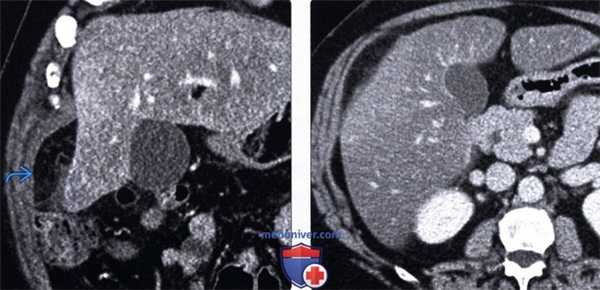

(Левый) У этого же пациента при многоплоскостной реконструкции на корональной томограмме определяется затененная жировая клетчатка сальника, симулирующая картину объемного образования. Обратите внимание на неизмененный тонкостенный желчный пузырь.

(Правый) Контрольное исследование три месяца спустя. Определяется медленное постепенное разрешение рентгенологических изменений.

(Слева) На аксиальной КТ с контрастным усилением определяется небольшое, содержащее жир объемное образование с гиперденсным «ободком» и воспалительными изменениями прилежащих тканей в правом нижнем квадранте сальника: «классический» внешний вид и локализация изменений при инфаркте.

(Справа) На корональной КТ с контрастированием у пациента после эндоскопической дистальной панкреатэктомии визуализируется содержащее жир объемное образование в левом верхнем квадранте сальника, представляющее собой массивный инфаркт. Инфаркты сальника после оперативного вмешательства могут быть весьма массивными.